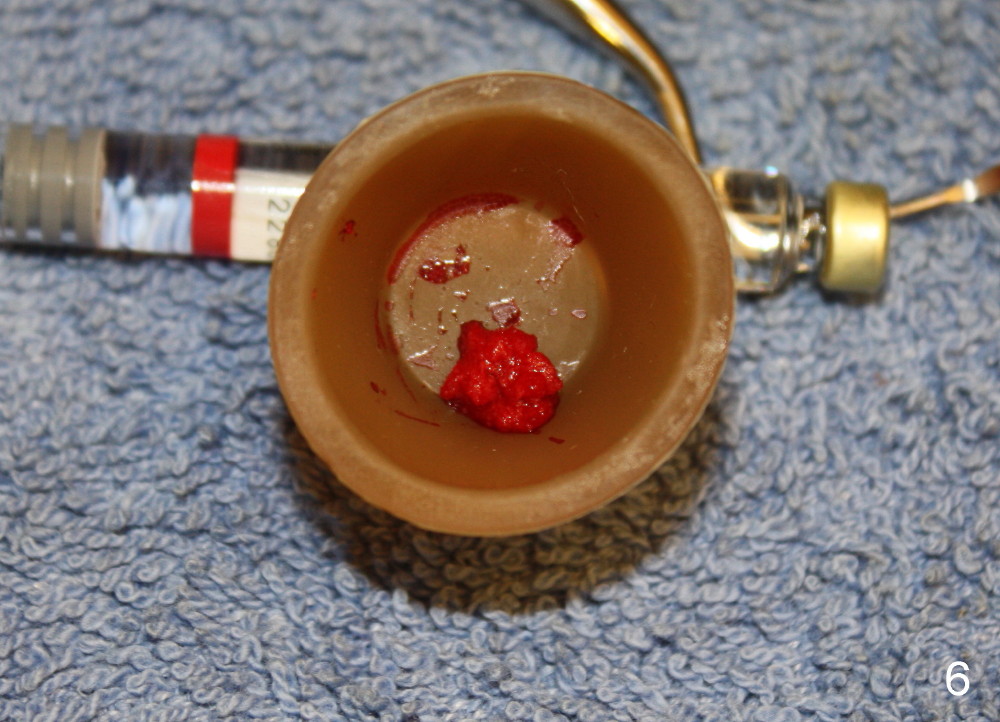

Luckily the patient returns for #31 implantation 4 months post socket preservation. Bone forms in the alveolus and above (Fig.1 black and white arrowheads, respectively). A 6 mm tissue punch is used to open the wound (Fig.2). Osteotomy forms using bone expanders, reamers and taps (Fig.3: 6x14 mm tap). Without infection, local anesthesia is more easily achieved than immediate implant when infection exists. The depth is controlled more readily with delayed implantation. Following adjustment of trajectory, a 7x11 mm implant is placed with insertion torque 60 Ncm (Fig.4 I). Fig.5 shows that the implant obliterates the wound; an abutment (A) is placed to retain perio dressing. With formation of new bone from socket preservation, insertion torque seems to be more easily obtained with the short implant. There is no space to re-use the harvested bone (Fig.6). The implant remains stable postop. Apparent new bone is forming toward the distal coronal threads 5 months postop (Fig.7). The bone around the implant remains stable 17 months post cementation (Fig.8), although there is an episode infection at the neighboring tooth (#30). The patient is more eager to have implants for the maxilla, since the flipper has lost. After implant placement at #7, the pain at #30 becomes more severe.